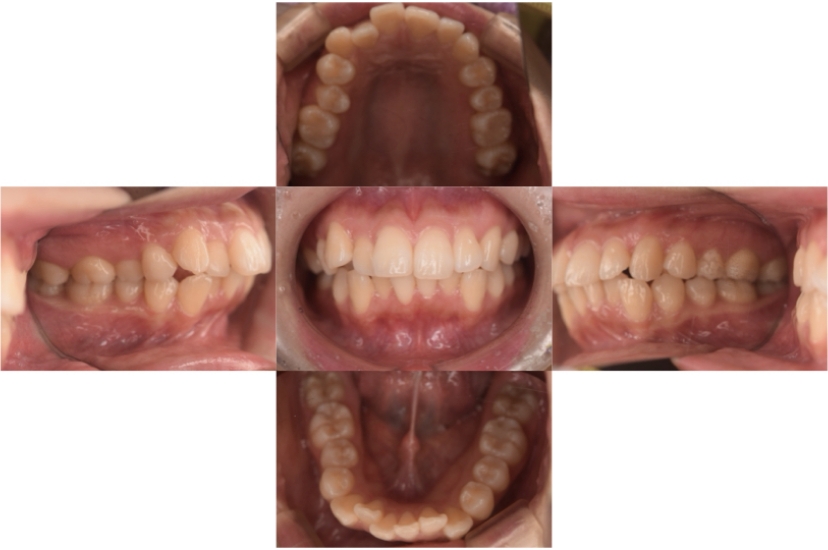

BEFORE

AFTER

症例3

叢生

抜歯

ブラケット矯正

症例解説

上下顎叢生(上下の前歯のガタガタ)のケースです。

装置はラビアル(上下表側)で、上下顎の小臼歯を4本抜歯を行っています。抜歯したスペースを使って、上下の前歯の後方移動と叢生(ガタガタ)の改善を行っています。

主訴 八重歯を治したい。

年齢・性別 25歳 女性

お住まいの地域 神奈川県川崎市

治療方針 抜歯スペースを利用して上前歯の叢生(ガタガタ)の改善

抜歯部位 上下顎左右第一小臼歯

使用装置 ラビアル(上下表側)、顎間ゴム

治療期間 1年11か月

治療回数 16回

リテーナー クリアリテーナー